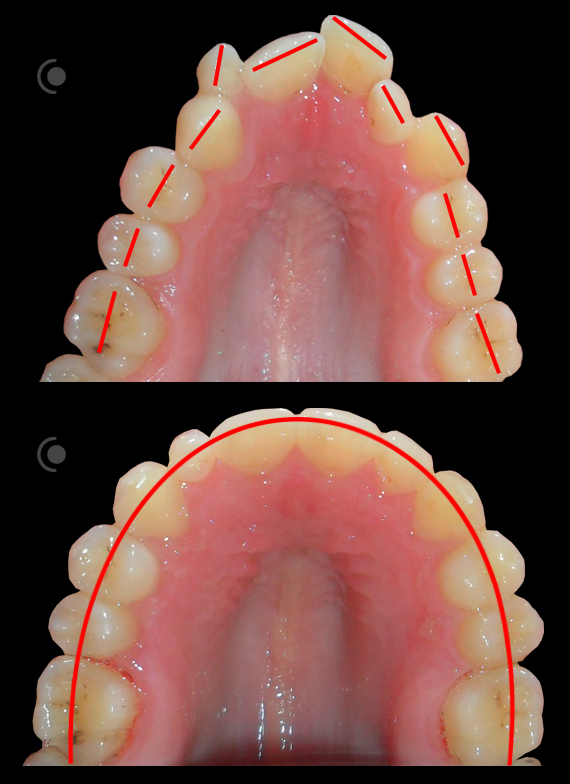

O našoj kvaliteti najbolje govore naši rezultati!

Centar za ortodonciju Petra Džapo